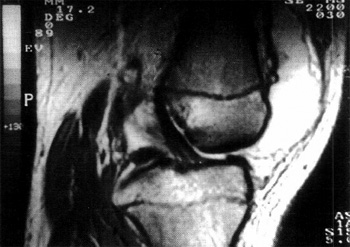

Fig. 3: Lesión Tipo I intrasubstancia, secuencia D.P.

TIPO II 0 MODERADAS:

Lesión que ya muestra alterada la estructura y los bordes del ligamento; ubicada en los tercios proximal o medio, involucra la mitad posterior del ligamento observado en el plano de perfil oblicuo. La alteración del borde posterior, por lo tanto es evidente. El sector anterior debe mostrarse indemne, con su característica hiposeñal. En los casos agudos las imágenes de R.M.N. muestran las características de las rupturas totales agudas, pero localizadas al sector comprometido del ligamento o sea engrosamiento focal e incremento de la señal de resonancia en todas las secuencias spin eco, mientras en los crónicos, la alteración se traduce en adelgazamiento ligamentario manifiesto con normoseñal en T2

Fig. 4: Lesión Tipo II, secuencia T1

Fig. 5: Lesión Tipo II, secuencia D.P.